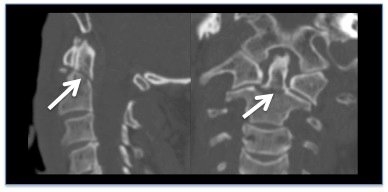

- tomografía computarizada de alta resolución de la columna cervical